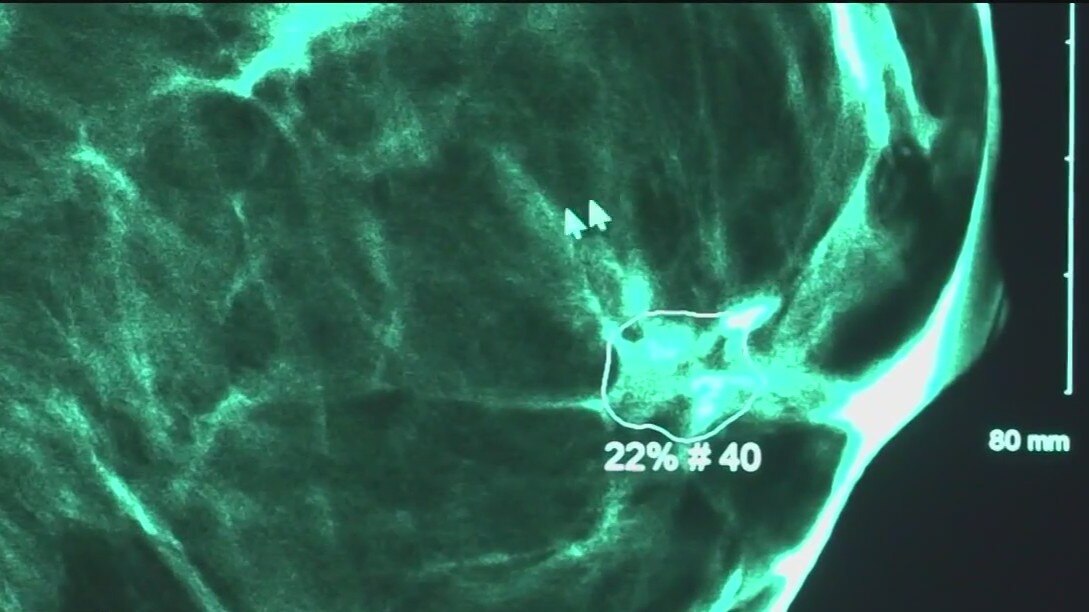

Artificial intelligence helping detect early signs of breast cancer in some US hospitals

Some hospitals have seen a 23% increase in breast cancer diagnoses since utilizing AI technology.

Doctors use AI to detect breast cancer earlier

They say it doesn't just stop at breast cancer, either. The artificial intelligence has proven capable of detecting brain cancer, lung cancer and prostate cancer as well. Sometimes, it catches the disease so early that patients are able to sidestep chemotherapy altogether.